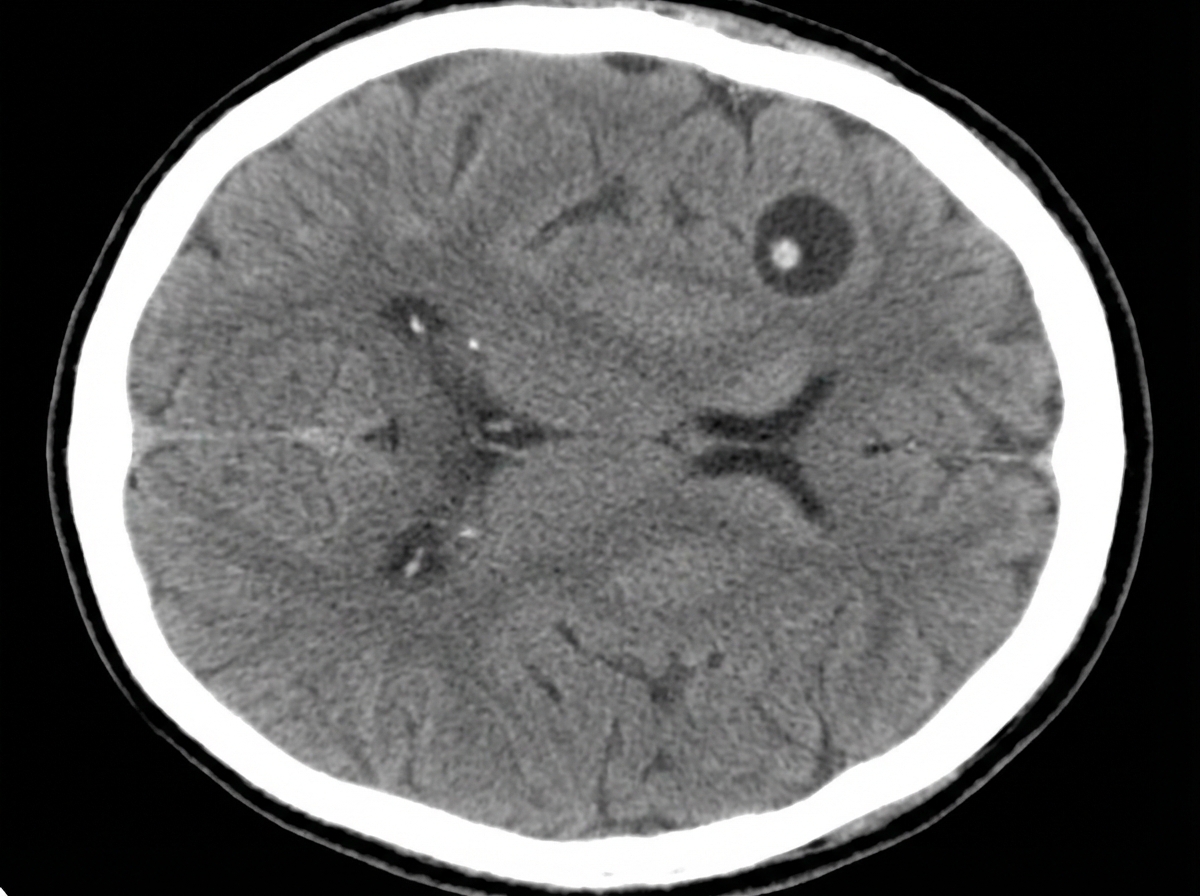

A 53-year-old woman with hypertension is brought to the emergency department 30 minutes after having a generalized, tonic-clonic seizure. She has had recurrent headaches and dizziness in the last 3 months. One year ago, she had diarrhea after a trip to Ecuador that resolved without treatment. She has not received any medical care in the last five years. She has smoked 1 pack of cigarettes daily for 20 years. Her temperature is 36°C (96.8°F) and blood pressure is 159/77mm Hg. Physical examination shows dysarthria and hyperreflexia. She is confused and oriented only to name and place. Four brain lesions are found in a CT scan of the brain; one of the lesions is shown. Which of the following is most likely to have prevented this patient's condition?